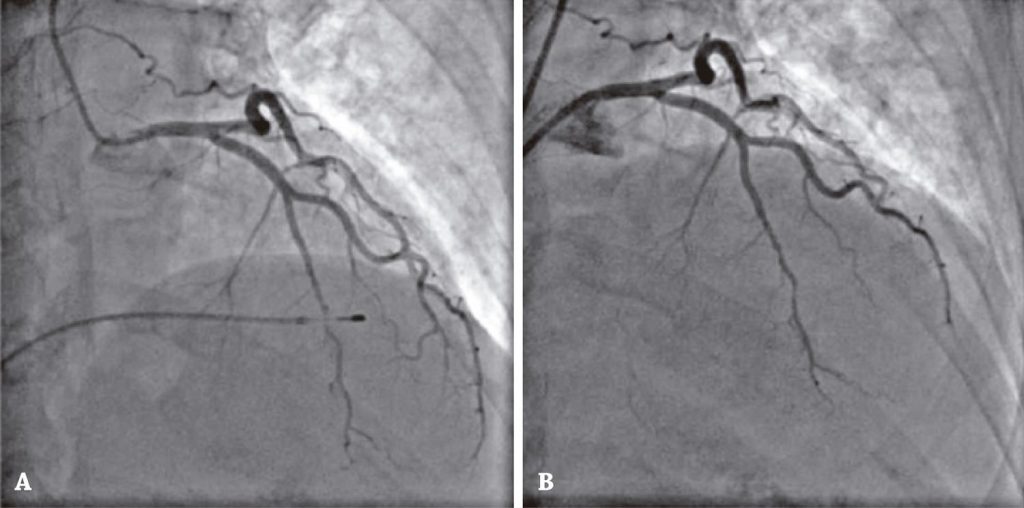

Foi admitida na unidade coronariana e evoluiu com queixa de tontura, sendo novamente identificado bloqueio AV de segundo grau tipo 2:1 e indicado implante de marca-passo provisório. A partir de então, após implante de marca-passo provisório transvenoso com acesso pela veia braquial, a paciente desenvolveu dor torácica e apresentou aumento dos níveis de troponina ultrassensível (305ng/mL; 12.529ng/mL; 3.525ng/mL; 1.158ng/mL; valor de referência superior de 60,00ng/mL).